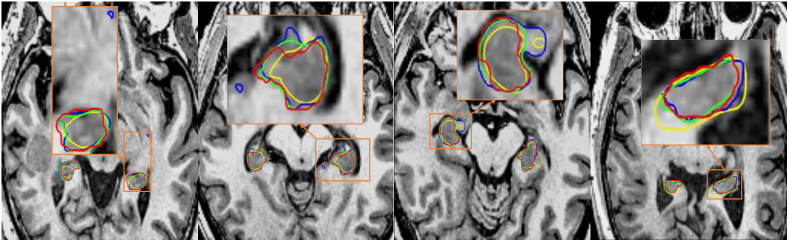

Refer to caption

Figure 5: Qualitative segmentation comparison on the hippocampus testing set. The red, blue, yellow and green contours represent the groundtruth annotation, training with segmentation only, training with SDM only, and training with SDM and segmentation jointly. In the first three columns, one can see that the segmentation-only results contain isolated or inaccurate false positive regions. In all columns, the model with joint training achieves best accordance with groundtruth annotation. Zoom in for better view.

We present a group of axial view SDM plots in Figure 4. One can observe that the learned SDM with only SDM training obtains smoothest contours, while the joint training of SDM and segmentation map predicts more accurate organ boundary. Overall, they both preserve the shape of hippocampus and align well with the groundtruth SDM. Such results prove that predicting SDM directly from the medical image input is feasible and reliable, where shape information is indeed captured during the learning process. Qualitative comparison of segmentation results is illustrated in Figure 5. As aforementioned, segmentation results trained with only segmentation output (blue contours) have false positives due to the lack of shape awareness. According to the results shown in Figure 5 and Table 1, segmentation by jointly training with SDM and binary map supervision get best performances. In conclusion, incorporating segmentation with SDM prediction indeed provides meaningful improvements and generates better single organ segmentation results.